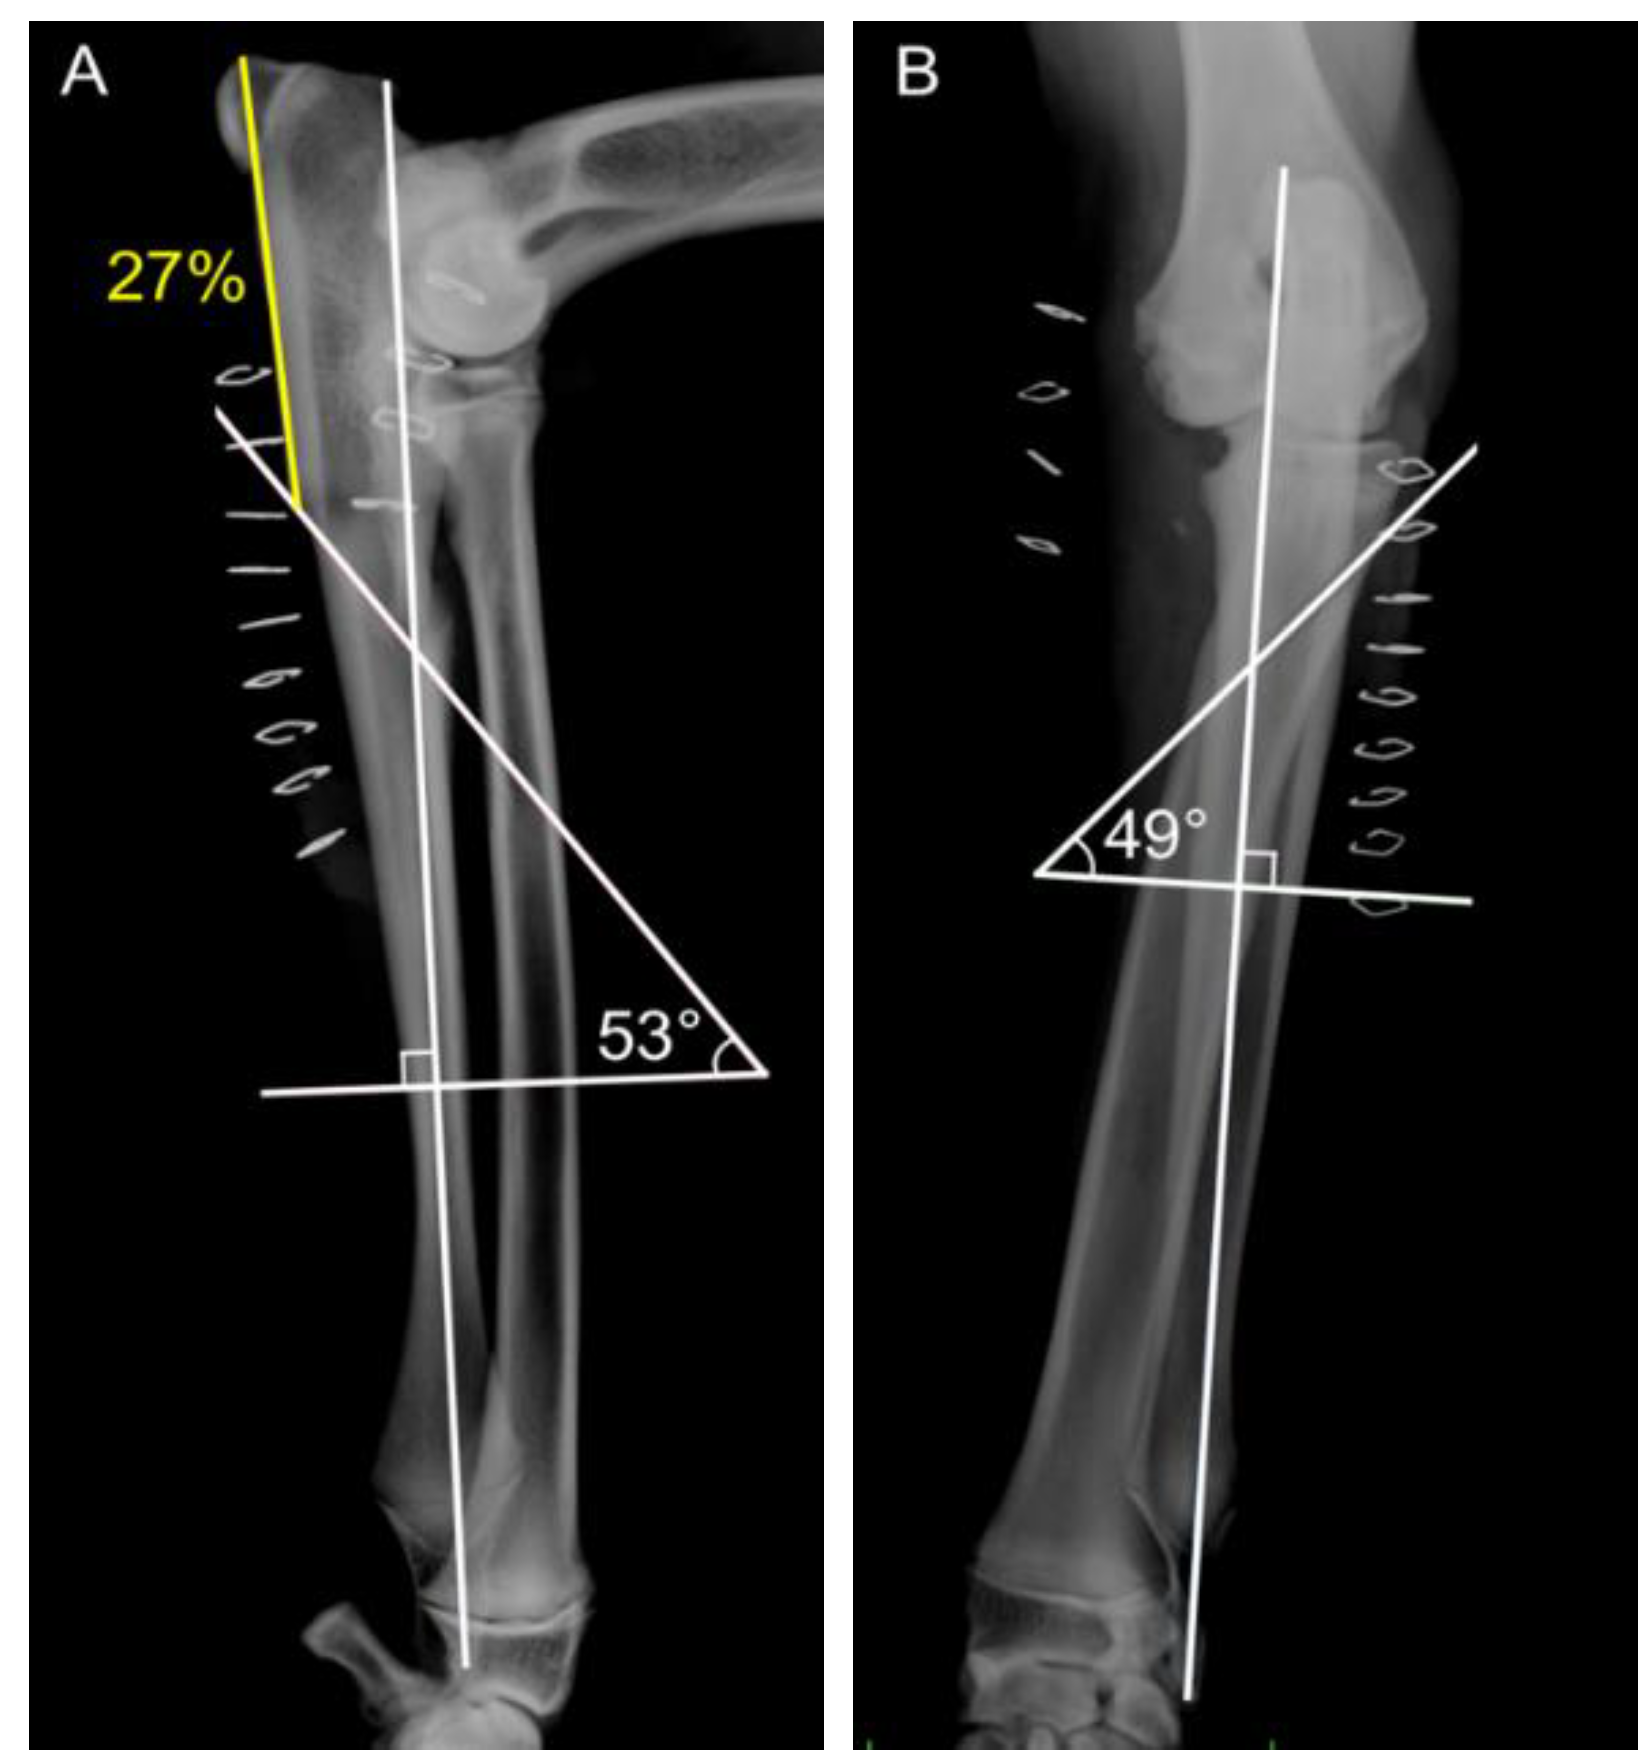

- Smith, T.J.; Fitzpatrick, N.; Evans, R.B.; Pead, M.J. Measurement of ulnar subtrochlear sclerosis using a percentage scale in Labrador Retrievers with minimal radiographic signs of periarticular osteophytosis. Vet. Surg. 2009, 38, 199–208. [Google Scholar] [CrossRef] [PubMed]

- Draffan, D.; Carrera, I.; Carmicheal, S.; Heller, J.; Hammond, G. Radiographic analysis of trochlear notch sclerosis in the diagnosis of osteoarthritis secondary to medial coronoid disease. Vet. Comp. Orthop. Traumatol. 2009, 22, 7–15. [Google Scholar]